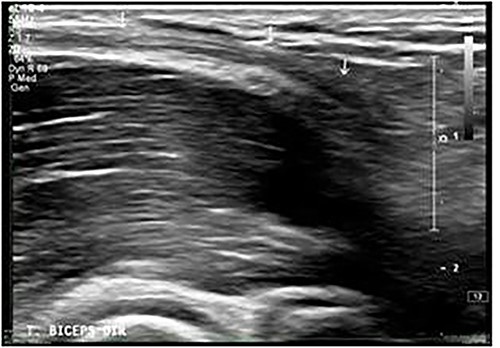

On physical examination (Fig. 1), the patient exhibited a visible deformity of the arm (inverted Popeye sign), a positive Hook test for distal biceps injury, symmetric elbow flexion strength, slightly decreased supination strength with pain, but with a complete range of motion for passive and active pronation-supination and flexion-extension. Ultrasonography and magnetic resonance imaging revealed a complete rupture of the distal biceps tendon (Figs 2–4).